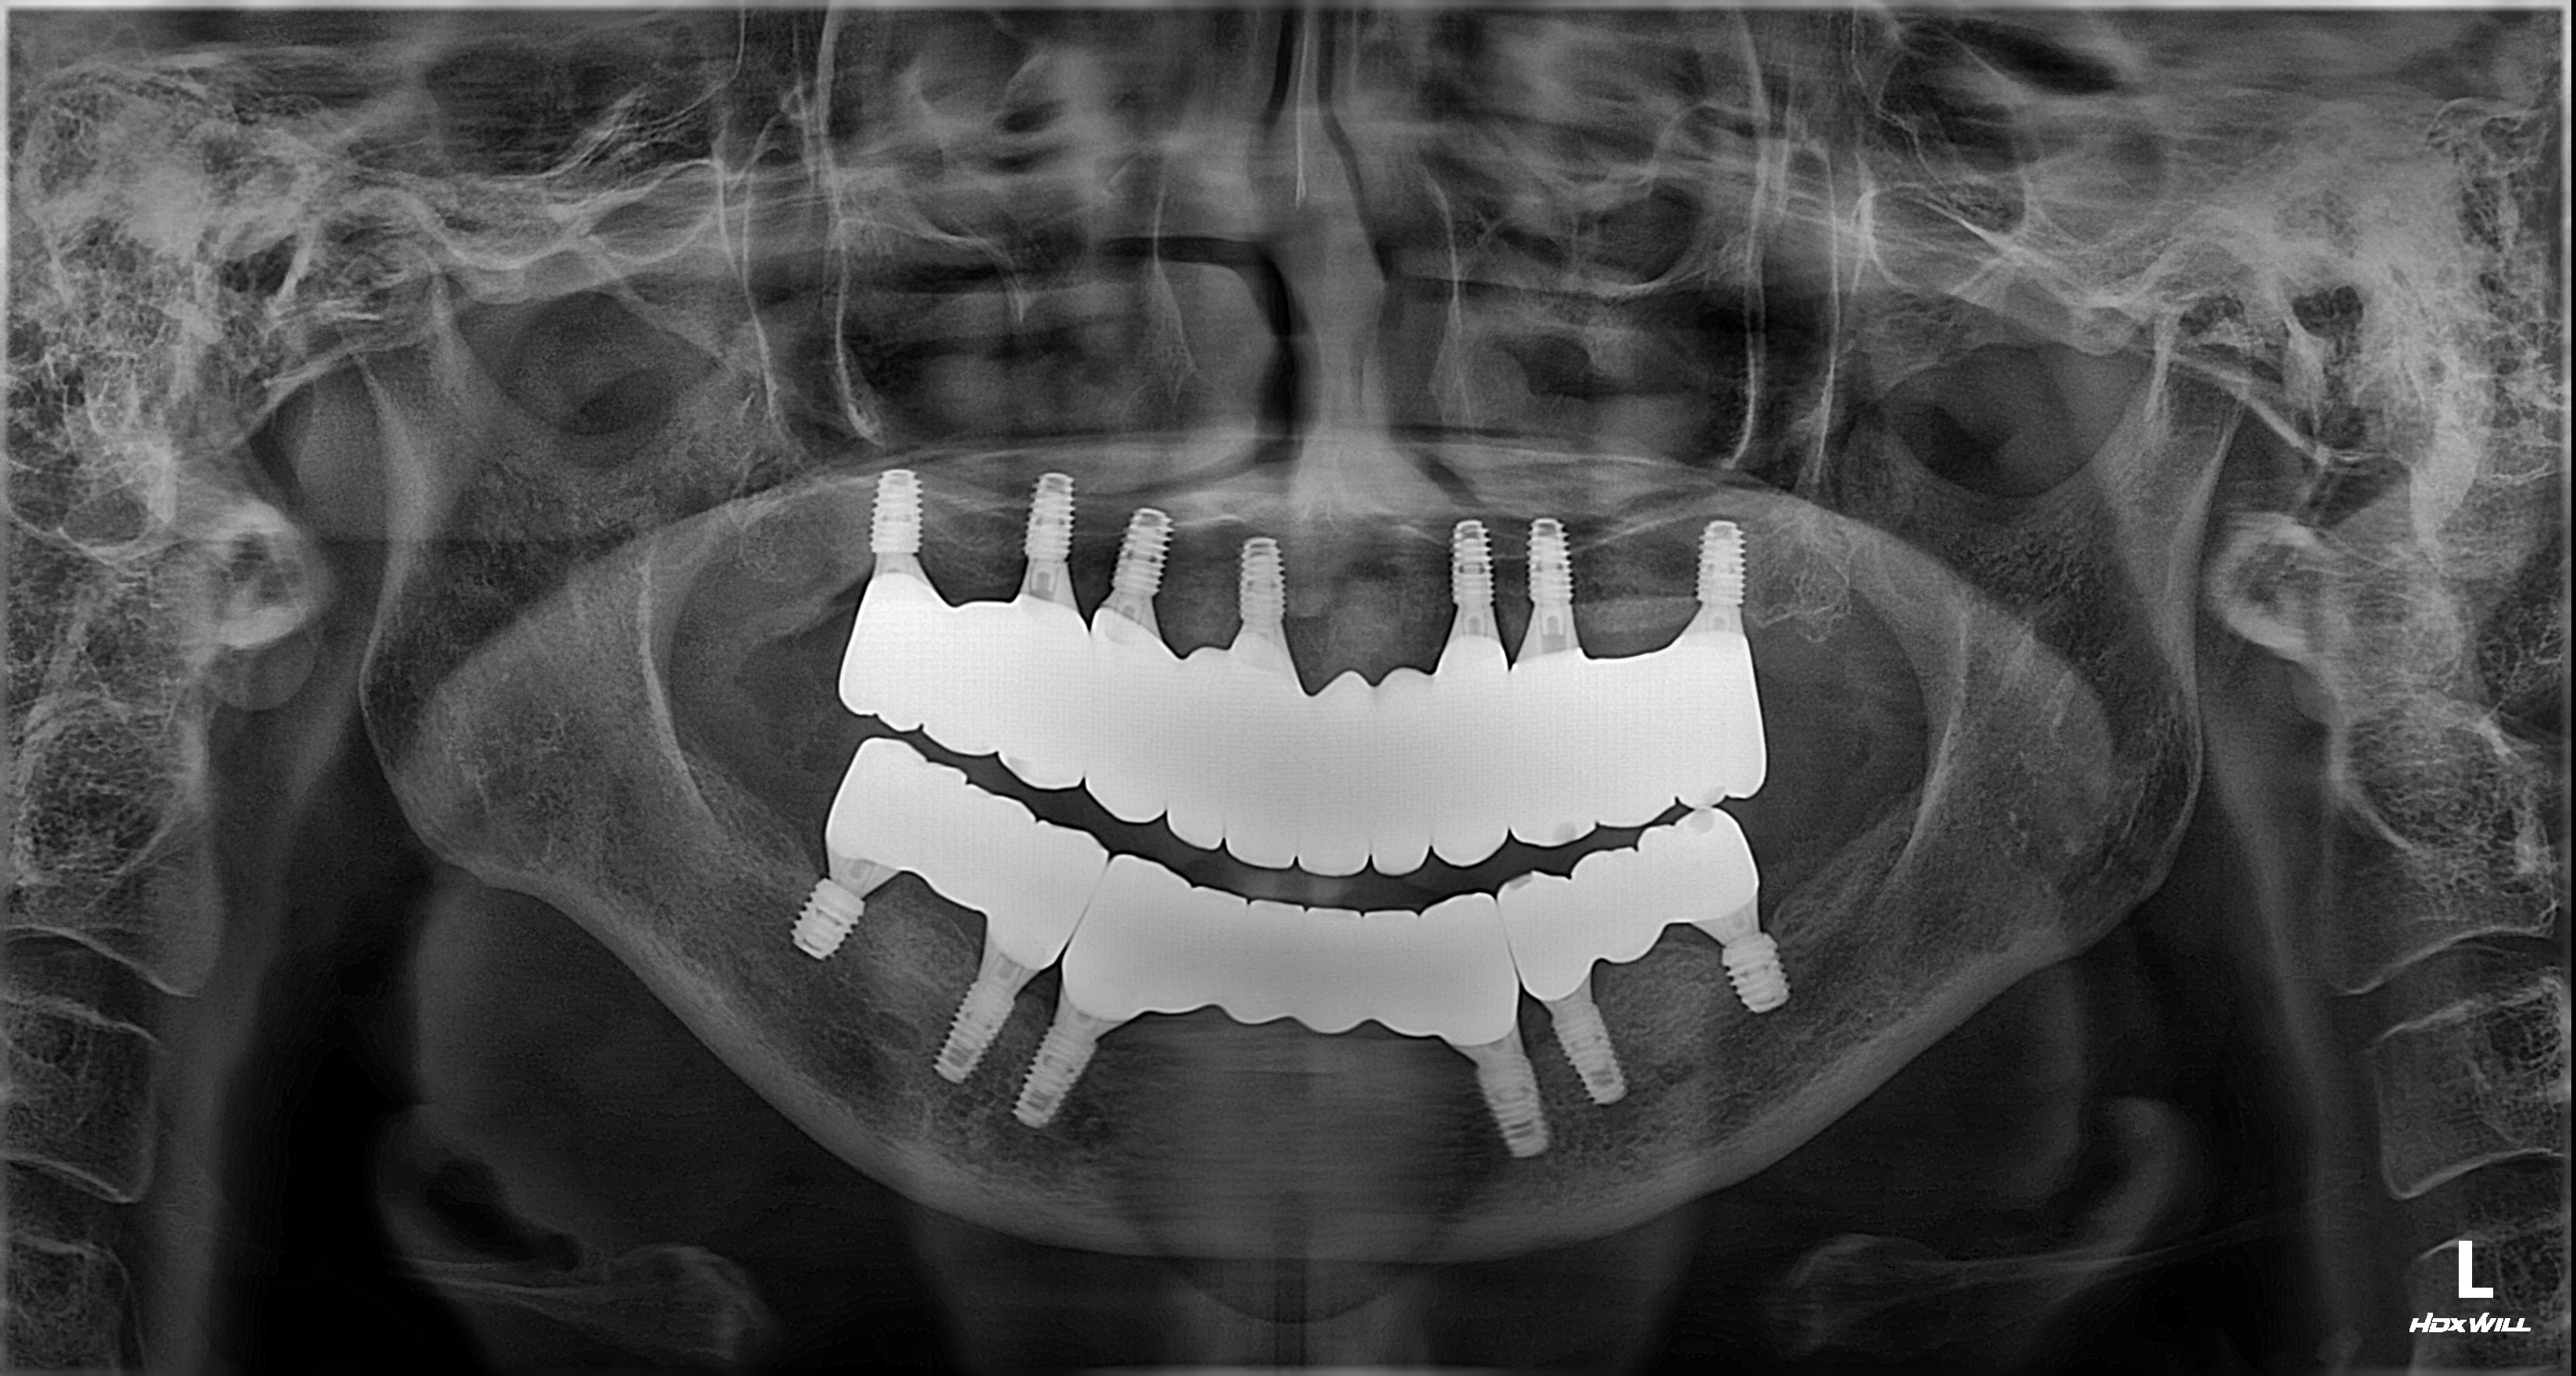

촬영일시: 2026.02.27. [ 치료기간: 2025년 04월 17일 ~2026년 02월 27일 ] ※ 365서울앞선치과의원의 모든 컬럼은 각 진료과 의료진이 직접 작성합니다. 365서울앞선치과의원 임상 케이스 게시물은 환자분께 의학적으로 정확하고 상세한 정보를 드리기 위해 각 진료과 의료진이 직접 작성하며, 모든 증례 사진은 본원 의료진이 직접 시술한 증례를 촬영한 것으로, 의료법 제23조, 제56조에 의거하며 환자분의 동의를 얻어 포스팅에 사용하였습니다. 또한 해당 케이스는 본 환자분의 치료 결과이며, 환자 상태에 따라 치료의 결과는 달라질 수 있습니다. |